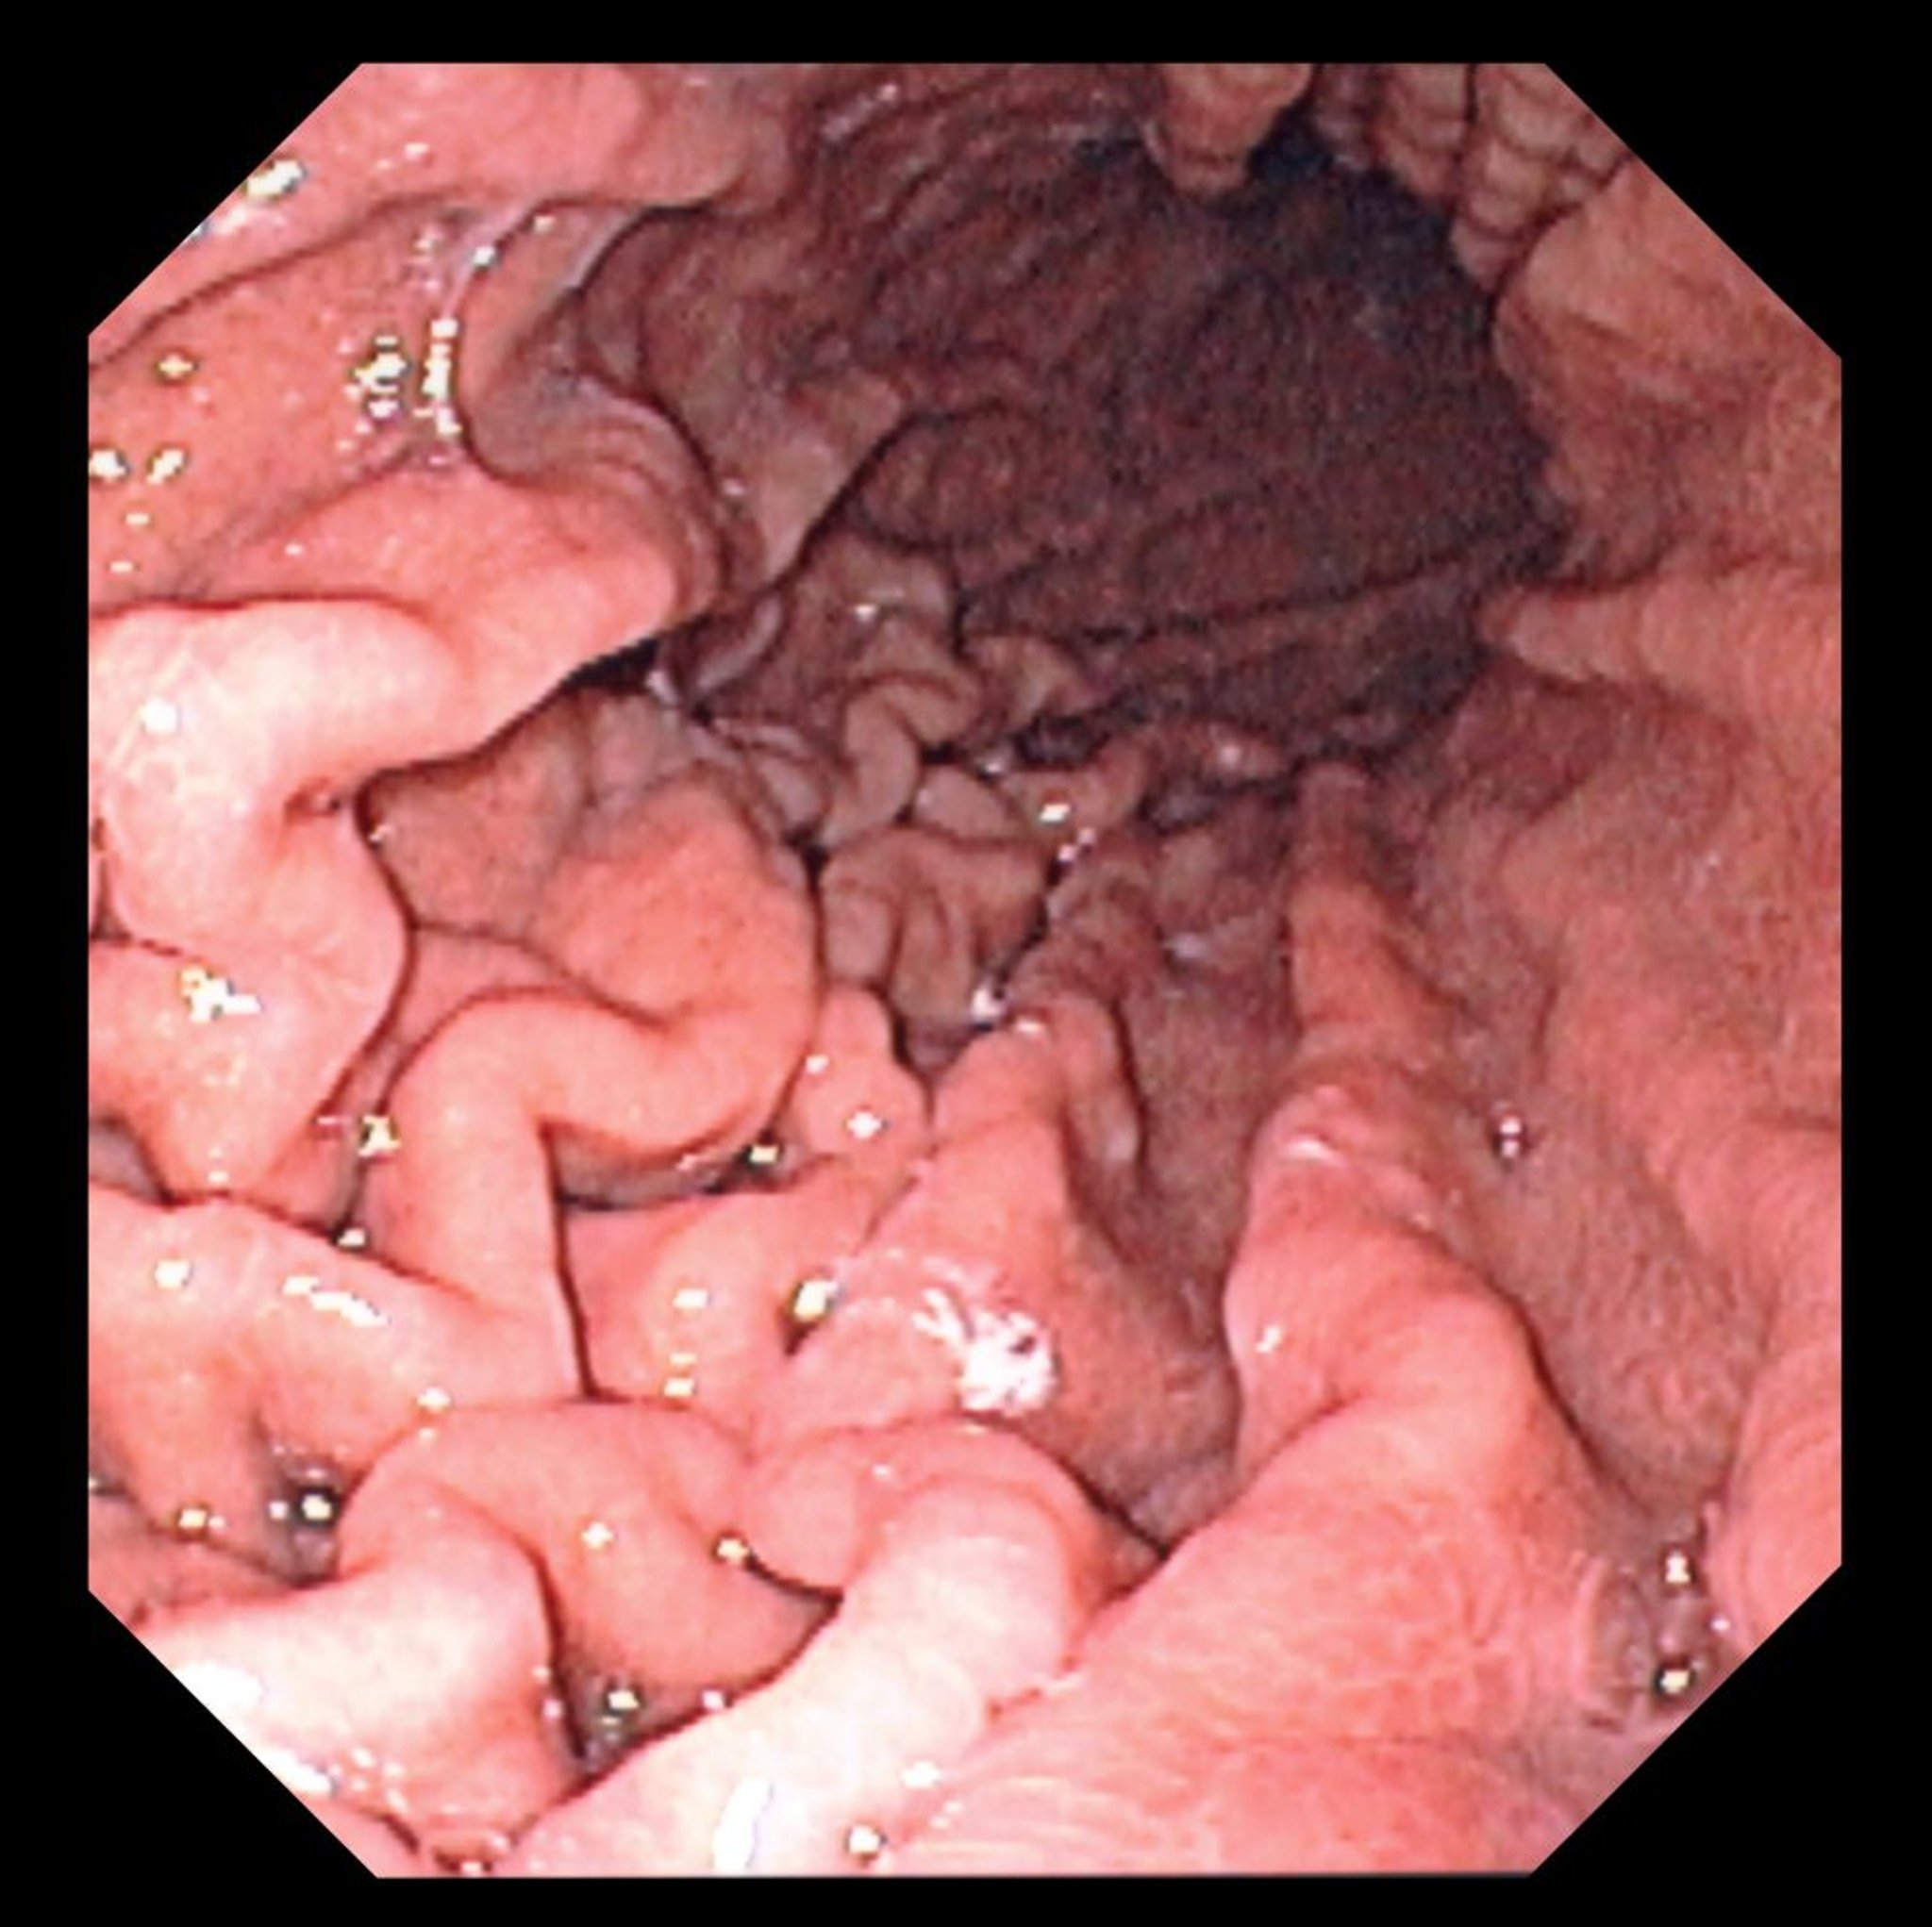

Questa foto mostra una vista endoscopica del fondo di uno stomaco normale con pieghe gastriche caratteristiche.